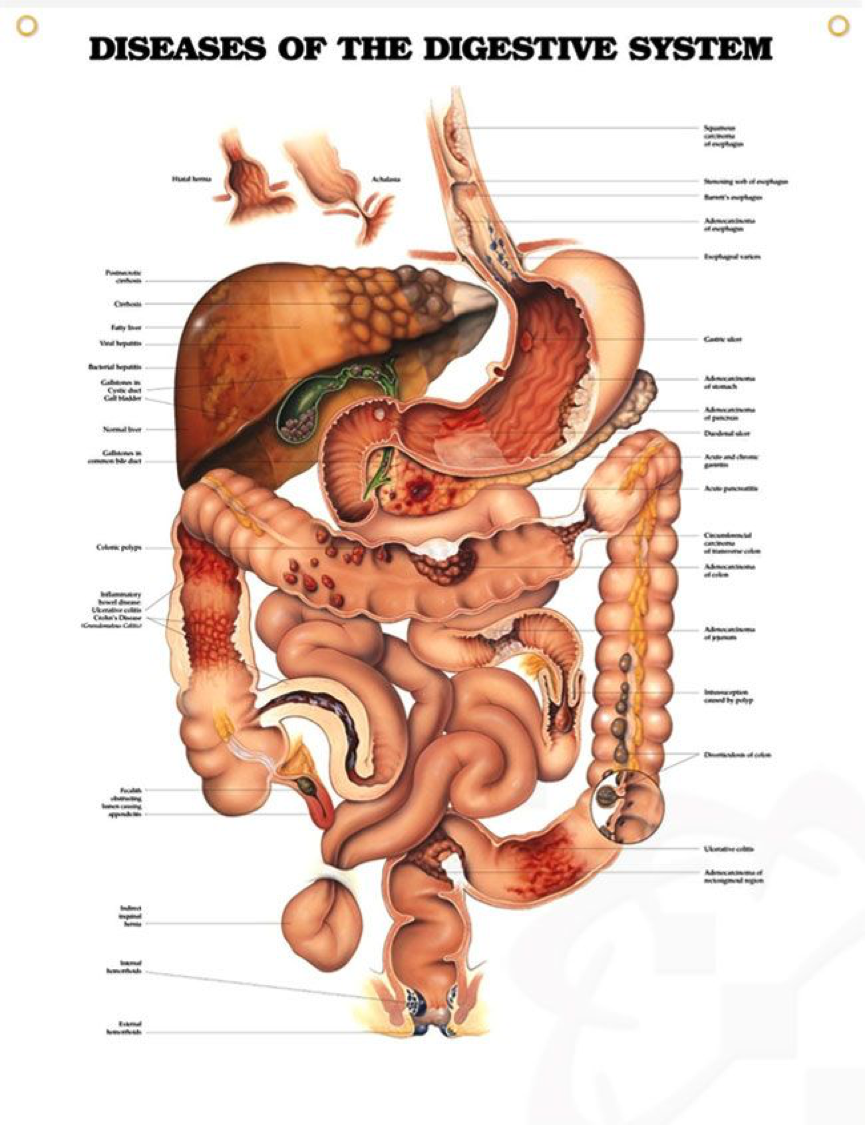

Digestive system pathologies are very common. The medical establishment classifies them into many various kinds related to the portion of the gut those diseases manifest in. However, the entire digestive system / digestive tract is a one complete system. It does not operate in the same fragmented way in which its diseases are being classified. Starting from the upper labium (the mouth lips) down to the lower labium (the rectum), the digestive tract is a complete system, where every part of it directly influences the function of its other parts. An inflammation found in any of the digestive tract portions actually implies the existence of an inflammation, in different degrees, throughout the digestive tract, and not only in the diagnosed diseased portion of it.

In order for treatment to be effective with long-term results, it must address the entire digestive tract, even the parts where the inflammation has not yet manifested. Whether the disease was diagnosed in the stomach, the small intestines or the large intestines, the treatment must include all these three sections. The reason for that is that while the inflammation has been diagnosed in just one area, it could be the result of a failure in another part of the digestive tract. Moreover, this diagnosed digestive disease might even be the result of a failure in other bodily systems altogether. Hormonal imbalance, malfunction of the hepatic system, thyroid malfunction, blood deficiency, improper blood circulation, etc., can all have a major influence on the digestive tract function. For example: chronic constipation can be the result of an out of synced action of the pelvic muscles relaxation and contraction during defecation. Another common example is stagnation of the liver, which often causes a deficiency in bile secretion, thereby, hindering the digestion of lipids.

The conventional classification does not differentiate between various stages of any digestive tract disease. Therefore, when applying treatment, the conventional classification does not take into account the severity or the extent of the damage to the particular diagnosed area of pathology in the digestive tract. The conventional treatment is the same, regardless of whether the pathology manifested is mild or severe. For example: peptic ulcer would be classified and treated the same, whether it is a minor inflammation in a small area of the stomach lining or an advanced bleeding ulcer with harsh symptoms – both of these cases would be classified as “peptic ulcer” and treated with the same chemical pills. Another common example is Crohn’s disease: in one case it could be in its initial stages, while another case could have advanced up to a bowel resection. Both of these cases would be classified as “Crohn’s disease” and treated the same.